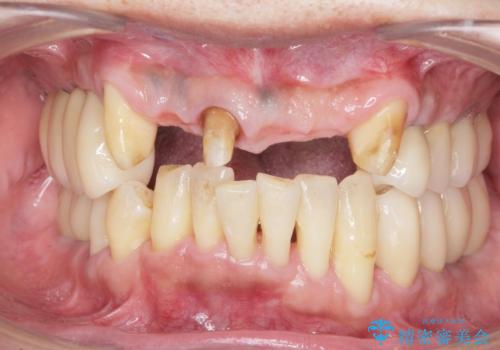

- 歯が全体的に揺れ始め、恐怖を感じ他院に相談に行ったところ、全体的な歯周病の問題・抜歯の必要性・入れ歯の提案を受け、入れ歯以外の選択肢を希望され来院されました。

全体的な歯周病検査を行い、多数の残すことのできない抜歯の必要な歯を認めたため、残せる歯に対しての徹底的な歯周病治療、失った歯に対しブリッジ・インプラント治療を全顎的に行っていくこととしました。